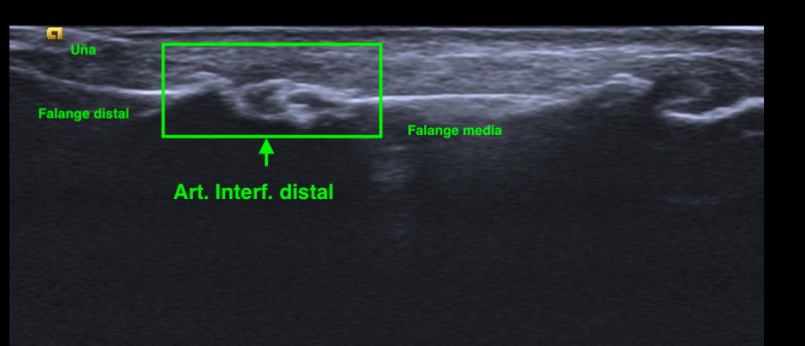

Bien, tanto en los nódulos de Heberden o de Bouchard o en los cambios de la Rizartrosis, lo que vamos a encontrar con el estudio ecográfico son afectaciones óseas en menor o mayor grado y cambios en las articulaciones de estas uniones óseas.

Podemos encontrar cambios en la superficie ósea de los huesos, en la cortical de los mismos, osteofitos, geodas y otras apariciones anómalas de esta ecoestructura ósea.

Aspecto ecográfico de cambios artrósicos producidos en Nódulo de Heberden.